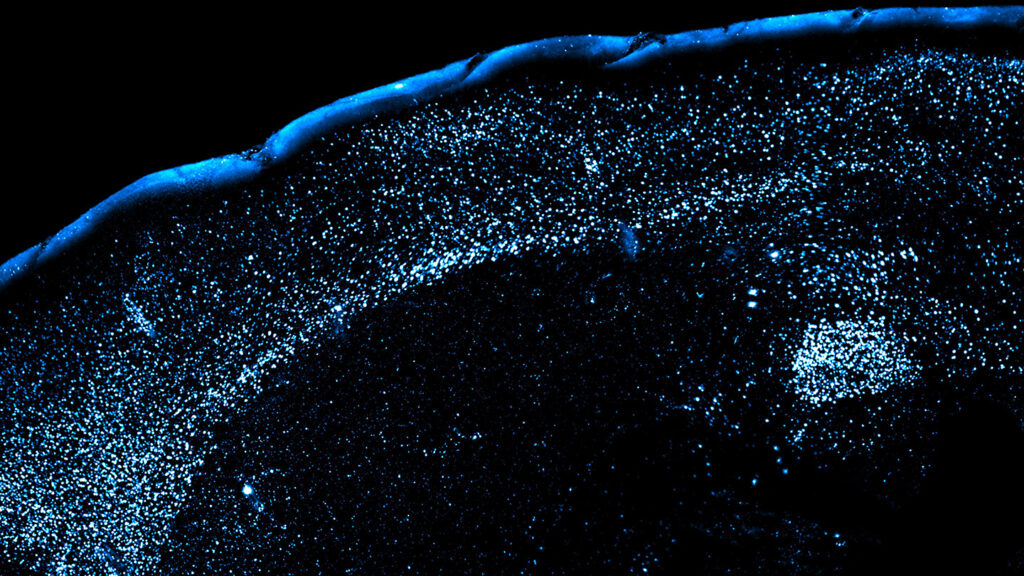

The team had mice drink grape Kool-Aid and, 30 minutes later, injected the rodents with lithium chloride to make them ill. Two days later, they gave the mice grape Kool-Aid again. The team ran many variations on this simple experiment and peeked inside the mice’s brains at each step. In some experiments, the researchers euthanized mice and made their brains transparent to image them in 3-D. In others, the researchers genetically engineered mice so their CGRP neurons could be turned on and off using light and used tiny electrodes to track the activity of small patches of the amygdala while the mice were alive.

When the mice got sick after drinking grape Kool-Aid for the first time, their CGRP neurons reactivated and dialed up the sensitivity of neurons in the amygdala that represented the flavor. Those same neurons reactivated when the mice encountered grape Kool-Aid again later, suggesting that reinforcement from CGRP neurons helps the amygdala remember dangerous foods. This effect didn’t occur in mice that had tasted grape Kool-Aid before without getting sick; only first-time exposures left a lasting impression. In humans, the novelty that cues us to remember food poisoning could be a bit more complex than taste alone: A spice blend, a new restaurant, or any other unfamiliar element of an eating experience can ick us out.